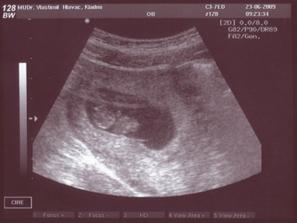

* 23.6.2009: 21 mm a slzy při pohledu na kmitající "ručky"